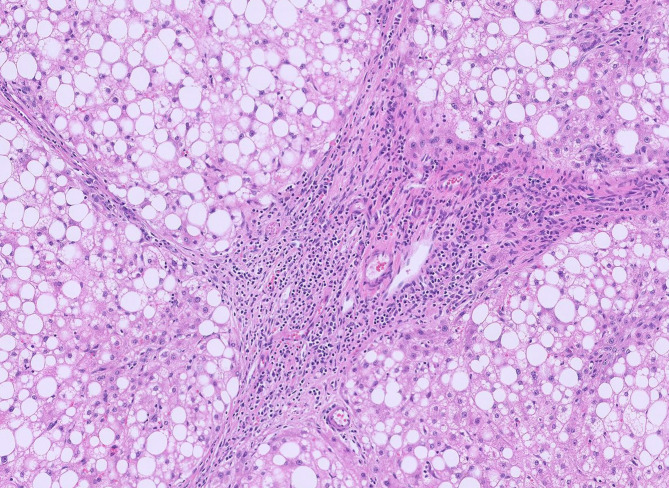

Case presentation: We describe a 33-year-old female who underwent excision of a pedunculated FNH. On gross examination, the lesion was lobular and vascular with homogenous tan-brown surfaces. Histological examination showed loss of normal liver architecture, abnormal intervening fibrous tracts, dysplastic arteries, and focal steatosis. Immunohistochemical staining with glutamine synthetase resulted in a branching, or "map-like" pattern. These findings were consistent with focal nodular hyperplasia. One of the most sensitive imaging techniques for diagnosing this lesion involves magnetic resonance imaging (MRI) with contrast, which discloses a homogenous mass that is hyperintense during the arterial phase with gradual decrease in intensity during the venous and equilibrium phases. The central stellate scar will often remain hyperintense for a prolonged period of time. On histology, normal hepatic architecture is lost to abnormal fibrotic bands and a characteristic stellate scar. Immunohistochemistry with glutamine synthetase uniquely highlights a map-like pattern that is not seen in other liver lesions.